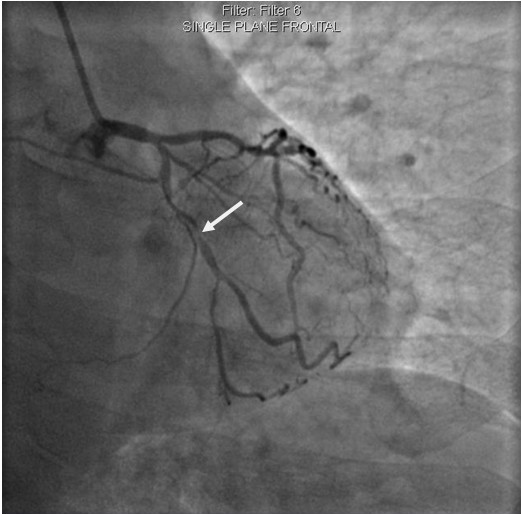

李先生右冠術(shù)前影像

李先生右冠術(shù)后影像

術(shù)前,翟光耀主任還親自為李先生復(fù)查冠狀動(dòng)脈造影,造影結(jié)果顯示:患者的前降支、回旋支、右冠等冠脈三支嚴(yán)重病變、嚴(yán)重鈣化,且均為彌漫性長(zhǎng)病變,最重處99%以上管腔極嚴(yán)重狹窄。翟主任仔細(xì)閱讀造影結(jié)果后指出:結(jié)合李先生的實(shí)際情況,雖然微創(chuàng)介入手術(shù)難度比較大,但仍可行;李先生心臟三支主干動(dòng)脈均存在極其嚴(yán)重的狹窄,每一支動(dòng)脈均至少植入2-3枚支架,根據(jù)患者的耐受情況,李先生可能需要分3次分別對(duì)三支動(dòng)脈進(jìn)行介入手術(shù);考慮到李先生路途遙遠(yuǎn),病情嚴(yán)重,不宜反復(fù)奔波,并且患者迫切要求能夠徹 底解決病痛,在病情允許的情況下,如果手術(shù)順利,爭(zhēng)取為患者進(jìn)行“一站式”手術(shù),一 次 性解決全部三支動(dòng)脈病變!